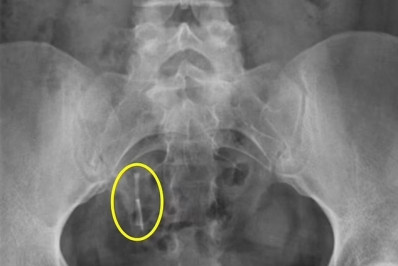

Raio-X realizado após um acidente de carro identificou o DIUReprodução / Daily Mail

Daniella Hampton, 29, encontrou, alojado no reto, um dispositivo intrauterino (DIU) que estava perdido dentro do seu corpo há 12 anos. Ele foi identificado por um raio-X feito depois que a mulher, que é dos Estados Unidos, sofreu um acidente de carro. A história foi publicada no jornal britânico "Daily Mail".

Daniella passou nove anos sem saber o que tinha acontecido com o DIU, até que ele foi encontrado na região que ela chamava atenção, em abril de 2021, após raio-X exigido por causa de um acidente de carro. Ele estava no cólon dela e migrou para lá depois de perfurar o útero. Uma cirurgia foi feita para retirá-lo cinco meses depois.